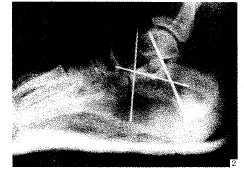

【摘要】 目的 评价手术治疗涉及关节内的跟骨骨折之疗效。方法 外侧入路,开放复位克氏针内固定。 结果 22例患者经过4~37个月的随访,其中优18例,良3例,差1例。结论 涉及关节面的跟骨骨折,只有恢复跟骨关节面的解剖形态,才能较好地恢复足的功能。